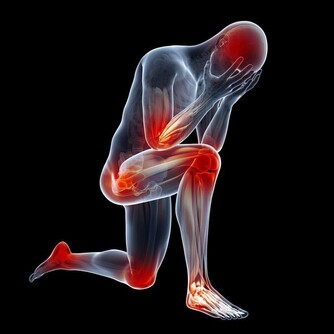

1、上腹不適

是胃癌中最常見的初發症狀,約80%患者有此表現,與消化不良相似,如發生腹痛,一般開始較輕微,且無規律性,進食後不能緩解,逐漸加重,可以為隱痛,鈍痛。部分可以有節律性疼痛,尤其胃竇胃癌更明顯,甚至進食或服藥可緩解。老年人痛覺遲鈍,多以腹脹為主訴。這些症狀往往不被患者所重視,就醫時也易被誤認為胃炎或潰瘍病。故中年患者如有下列情況,應給予進一步檢查,以免漏診:A.既往無胃病史,但近期出現原因不明的上腹不適或疼痛,經治療無效;B.既往有胃潰瘍病史,近期上腹痛的規律性改變,且程度日趨加重。如症狀有所緩解,但短期內又有發作者,也應考慮胃癌的可能性,及時作進一步檢查。